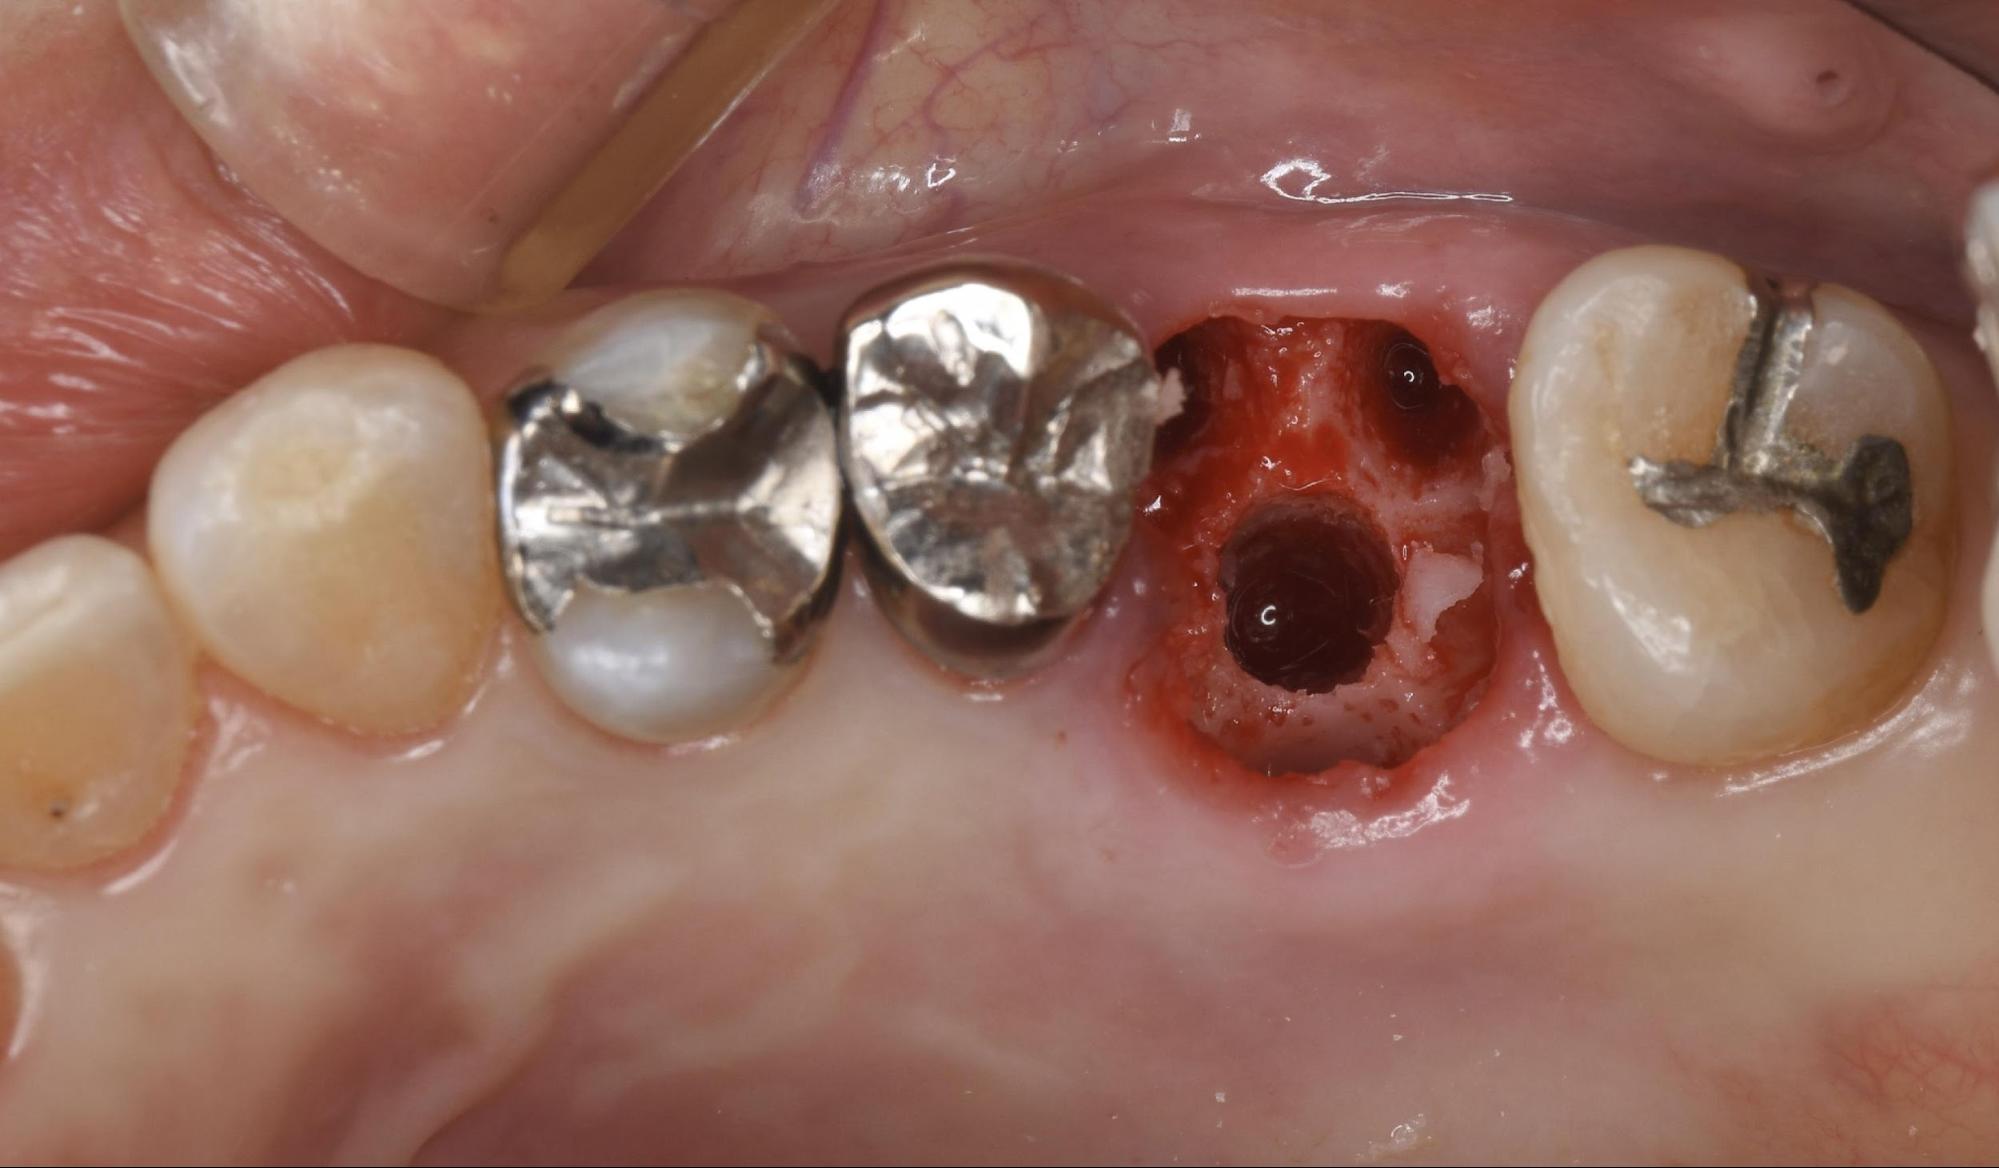

①丁寧な抜歯

周囲の骨を傷つけないよう、マイクロスコープ(歯科用顕微鏡)なども活用しながら、慎重かつ丁寧に歯を抜きました。インプラントを成功させるためには、この「周囲の骨を残すこと」がとても重要です。

② Xガイドによるフラップレス埋入

ここからが当院のデジタル技術の真骨頂です。「Xガイド」を使用し、歯ぐきを切らずにインプラントを埋入していきます。

本来、歯ぐきを切らないフラップレス手術は、骨を直接見ることができないため、歯科医師の経験や勘に頼る部分があり、リスクも伴う高度な術式です。しかし、Xガイドを使うことで、そのリスクを軽減できます。